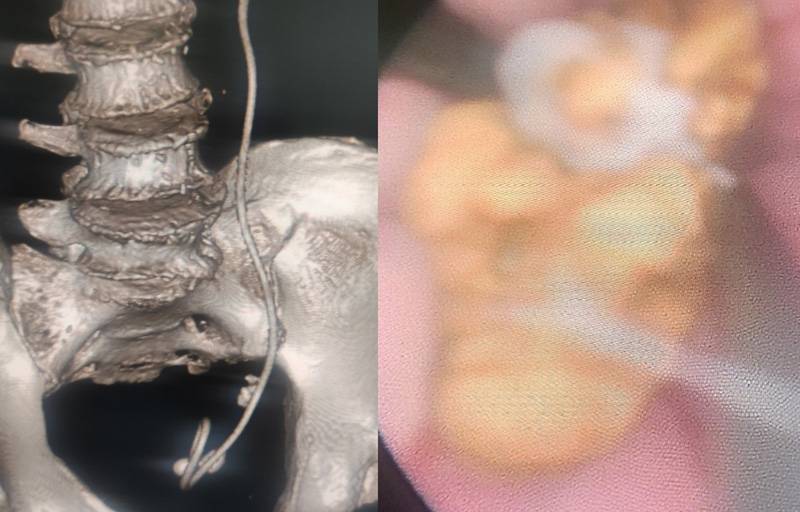

Đến năm 2022, bệnh nhân nhập viện trong tình trạng sốt, nhiễm trùng huyết tiêu điểm đường tiết niệu. Bệnh nhân được tiến hành thăm khám, chụp CTscanner phát hiện sỏi niệu quản, sỏi bàng quang, sonde JJ niệu quản trái, thận trái ứ nước độ 3 và suy thận độ IIIA.

Sau quá trình hồi sức tích cực cho bệnh nhân tạm ổn, nước tiểu trở về trạng thái bình thường. Qua hội chẩn, các bác sĩ chỉ định phẫu thuật rút sonde JJ đã bỏ quên 4 năm cho bệnh nhân, đồng thời, tán sỏi niệu quản trái 2 viên, tán sỏi bàng quang 2 viên.

Sỏi to như quả trứng gà tích tụ quanh ống sonde JJ bỏ quên suốt… 4 năm trong bụng